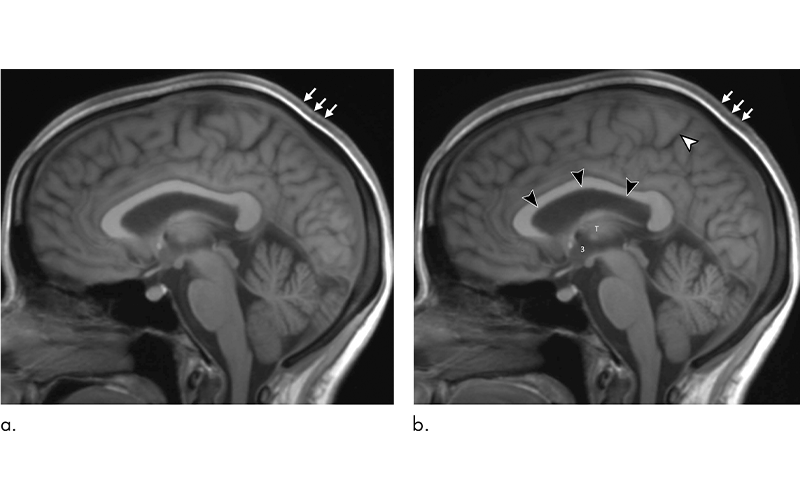

To find out more, Dr. Kramer and colleagues performed brain MRI on 11 astronauts, including 10 men and one woman, before they traveled to the ISS. The researchers followed up with MRI studies a day after the astronauts returned, and then at several intervals throughout the ensuing year.

MRI results showed that the long-duration microgravity exposure caused expansions in the astronauts’ combined brain and cerebrospinal fluid (CSF) volumes. The combined volumes remained elevated at one-year postflight, suggesting permanent alteration.

“What we identified that no one has really identified before is that there is a significant increase of volume in the brain’s white matter from preflight to postflight,” Dr. Kramer said. “White matter expansion in fact is responsible for the largest increase in combined brain and cerebrospinal fluid volumes postflight.”

MRI also showed alterations to the pituitary gland. Most of the astronauts had MRI evidence of pituitary gland deformation suggesting elevated intracranial pressure during spaceflight.

“We found that the pituitary gland loses height and is smaller postflight than it was preflight,” Dr. Kramer said. “In addition, the dome of the pituitary gland is predominantly convex in astronauts without prior exposure to microgravity but showed evidence of flattening or concavity postflight. This type of deformation is consistent with exposure to elevated intracranial pressures.”

The researchers also observed a postflight increase in volume, on average, in the astronauts’ lateral ventricles. However, the overall resulting volume would not be considered outside the range of healthy adults. The changes were similar to those that occur in people who have spent long periods of bed rest with their heads tilted slightly downward in research studies simulating headward fluid shift in microgravity.